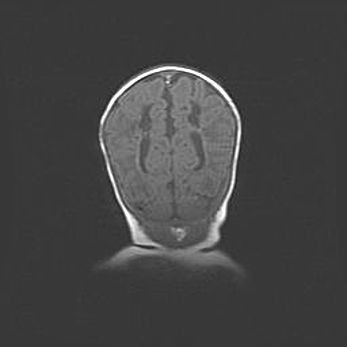

Сообщающаяся гидроцефалия. Кистозная энцефаломаляция головного мозга.

Возраст: 3 месяца 4 дня

Вес: 3100 г

Пол: женский

Окружность головы: 34 см

Срок гестации: 31 неделя

Кистозная энцефаломаляция головного мозга - одна из форм поражения головного мозга в детском возрасте. Характеризуется возникновением множественных и распространённых кист в коре, белом веществе и подкорковых образованиях головного мозга у плодов, новорождённых и детей раннего возраста. Развитие кистозной энцефаломаляции связано с внутриутробной асфиксией и гипотонией, родовой травмой, тромбозом синусов, пороками развития сосудов, инфекциями, сепсисом и другими причинами. Наиболее значимые инфекционные агенты: вирусы простого герпеса, цитомегалии, краснухи, токсоплазмы, энтеробактерии, золотистый стафилококк и другие.